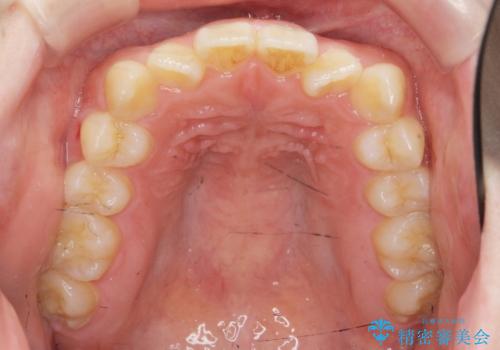

- 「前歯のねじれ、見た目を改善したい。」と矯正治療を希望され来院されました。

マウスピース矯正では改善の難しい前歯のねじれを前歯の部分ワイヤー矯正で改善したのち、インビザライン矯正を行い歯列を整えます。

インビザラインを行う前に前歯の部分矯正を行ったことで、しっかりとねじれが取れ整った歯列へと仕上げることが出来ました。